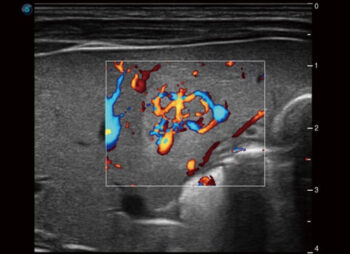

Color 3D

Өнгөт болон хүчирхэг Доплерийн горимд ашиглах боломжтой Color 3D нь цусны урсгалд дэвшилтэт дүрслэлийг ашиглан судасны сүлжээг хурд, чиглэлийн мэдээлэл, ялангуяа хүйн холбоотой илүү ойлгомжтой, байгалийн гемодинамик дүрслэлийг бий болгодог.